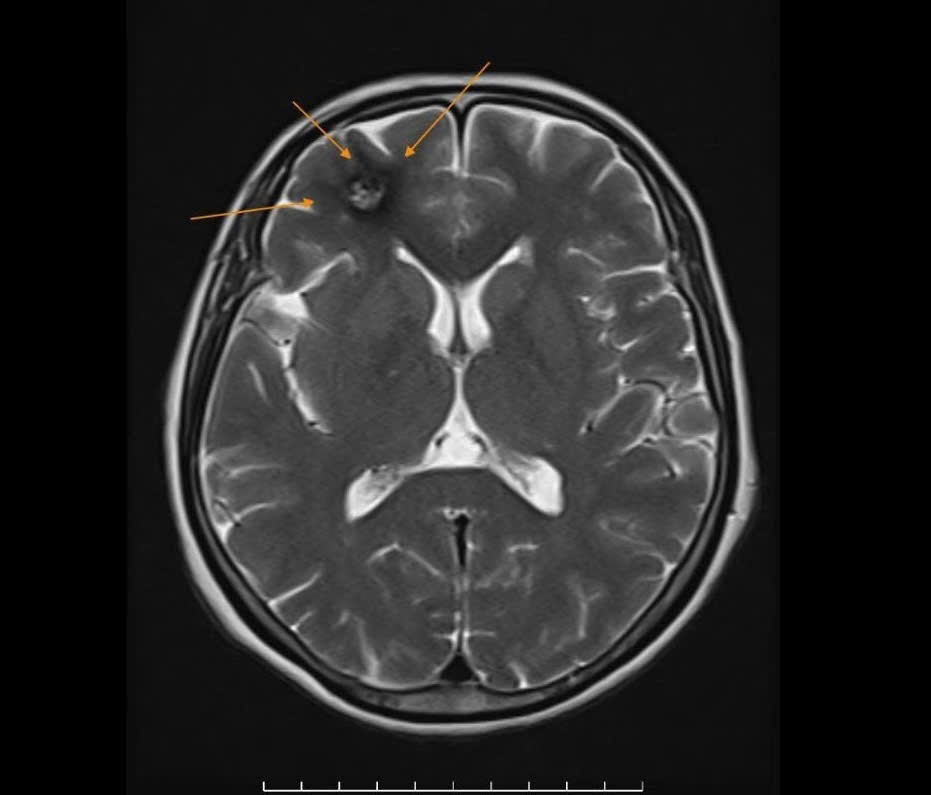

Trước đó, người bệnh đã chụp cắt lớp vi tính (CT scanner) sọ não tại một cơ sở y tế khác nhưng không phát hiện bất thường. Sau khi thăm khám, bệnh nhân được bác sĩ tư vấn chụp cộng hưởng từ sọ não (MRI 1.5 Tesla) tại Bệnh viện Đa khoa Quang Thành, kết quả cho thấy:

U máu thể hang (Cavernoma) có biến chứng xuất huyết giai đoạn bán cấp.

Tổn thương này có nguy cơ gây co giật hoặc tái xuất huyết; nếu không được phát hiện và theo dõi sớm có thể để lại hậu quả nặng nề.